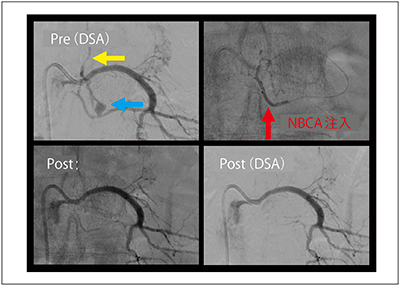

根静脈にシャントを形成するタイプがあるため,5Frシェファードフックカテーテルを左第3腰動脈に誘導して撮影すると,シャントに続く輸出静脈血管を認めた。Marathon/Tenrou10にてシャントを越えて輸出静脈血管まで誘導し,よく温めた20%NBCA0.1mLを注入したところ,DSAにてシャントおよび輸出静脈血管は描出されなくなった(図7)。

図7 IVRによる治療